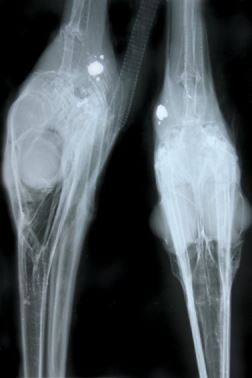

Deze voormiddag werd er een buizerd binnengebracht op het Natuurhulpcentrum. Wandelaars hadden de roofvogel langs een bospad in Meeuwen gevonden. Ze konden het dier gemakkelijk vangen.

In eerste instantie was het niet onmiddellijk duidelijk wat er met de roofvogel aan